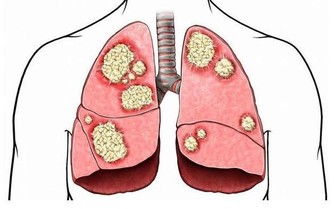

如何幫助肺部排毒?霧霾的存在讓我們越來越重視肺部的健康問題,從而也引伸到了肺部排毒的問題。

該如何養護我們的肺部,幫助肺部排毒,來看看中醫有什麼方法。

中醫上主張就要好好的保護好肺部,畢竟一旦肺部受到損傷,也會導致疾病的發生。

中醫認為,「肺為嬌臟」,「溫邪上受,首先犯肺」,肺是最容易受到外來有害物質侵害的臟器。

肺部有毒的表現症狀

肺毒的原因:肺毒也叫氣毒,主要和空氣品質有關,

肺毒的表現:呼吸不暢、胸悶、咳痰。